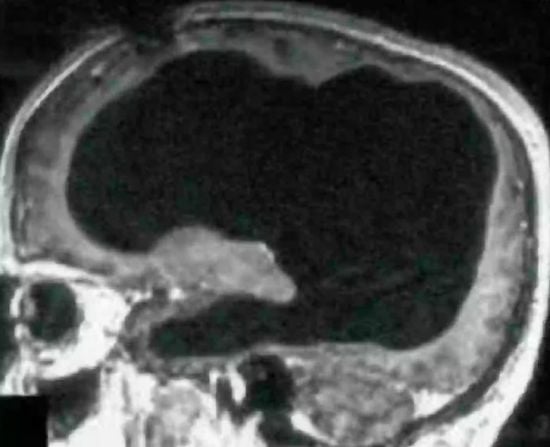

Чоловік випадково виявив, що живе з половиною мозку – фотоВід mik / 21.02.2025 Пацієнт звернувся до лікарні після того, як страждав на поширений симптом.